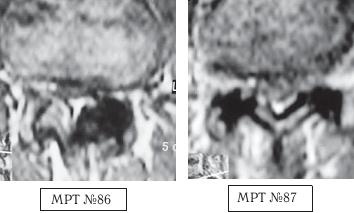

На МРТ № 86 наблюдается кровоизлияние (тёмное пятно на МРТ) в полость левого дугоотростчатого сустава — как следствие после лечения у мануального терапевта, который пытался «вправить выпавший диск».

На МРТ № 87 наблюдаются кровоизлияния в полости обеих дугоотростчатых суставов. Этот случай связан уже с другим пациентом, другим мануальным терапевтом, однако с тем же неутешительным результатом — снова кровоизлияние!

К сожалению, такие осложнения после мануальной терапии встречаются довольно часто. Их причина банальна — всего лишь попытка мануального терапевта устранить у пациента так называемую сублюксацию или «функциональный блок». Зачастую результат такого воздействия — кровоизлияние в полость травмированных дугоотростчатых суставов. Напомню, что внутренний слой суставной капсулы дугоотростчатых суставов имеет множество синовиальных ворсинок, богатых кровеносными сосудами. После травмы, когда кровь заполняет полость суставов, у пациента возникает боль, ограничение и болезненность движений вплоть до утраты способности пациента самостоятельно передвигаться.

Так вот, во время манипуляций мануального терапевта (внешней силы, воздействующей на потолок) происходит сдавление суставных поверхностей с одной стороны (в нашем образном сравнении потолок, к примеру с левой стороны комнаты, прижимается к полу). Жидкость, естественно, по законам физики, смещается в противоположную от локального напряжения сторону, слегка выпячивая соответствующую стенку суставной капсулы (правую стенку комнаты). Затем, с ещё большим усилием и с определённым напряжением мануальный терапевт начинает резко перемещать нагрузку в другую сторону (внешняя сила, прижимающая потолок к полу, перемещается слева направо). В момент манипуляции сустав «перекатывается» через несжимаемую внутрисуставную жидкость, перенося локальное напряжение в противоположную сторону данного сустава (к правой стенке комнаты). В этот момент жидкость соответственно перемещается под большим давлением на большой скорости в противоположную сторону (от правой стенки комнаты в левую), ударяясь о стенку капсулы (левую стенку) и растягивая её. В момент гидроудара при значительном прогибе суставной капсулы и получается характерный хруст — образовавшаяся звуковая волна (в слышимом человеческим ухом диапазоне частот). Напомню, что гидравлический удар образуется из-за резкого скачка давления в данной жидкости и вызван очень быстрым изменением скорости потока этой жидкости за очень малый промежуток времени. Именно такой гидроудар с характерным звуком, образовавшийся после соответствующих манипуляций мануального терапевта и порождает микротравматизацию суставной капсулы с микронадрывами, участками перерастяжения, микротрещинами (в том числе с участками кровоизлияния, которые хорошо видны в лабораторных условиях под микроскопом на соответствующих образцах данной ткани). А при значительных кровоизлияниях это уже можно наблюдать при диагностическом обследовании (МРТ).